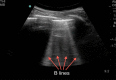

A novel coronavirus (2019-nCoV) was identified as the cause of a cluster of pneumonia in Wuhan, China, at the end of 2019. Since then more than eight million confirmed cases of coronavirus disease 2019 (COVID-19) have been reported around the globe. The current gold standard for etiologic diagnosis is reverse transcription-polymerase chain reaction analysis of respiratory-tract specimens, but the test has a high false-negative rate owing to both nasopharyngeal swab sampling error and viral burden. Hence diagnostic imaging has emerged as a fundamental component of current management of COVID-19. Currently, high-resolution computed tomography is the main imaging tool for primary diagnosis and evaluation of disease severity in patients. Lung ultrasound (LUS) imaging has become a safe bedside imaging alternative that does not expose the patient to radiation and minimizes the risk of contamination. Although the number of studies to date is limited, LUS findings have demonstrated high diagnostic sensitivity and accuracy, comparable with those of chest computed tomography scans. In this note we review the current state of the art of LUS in evaluating pulmonary changes induced by COVID-19. The goal is to identify characteristic sonographic findings most suited for the diagnosis of COVID-19 pneumonia infections.